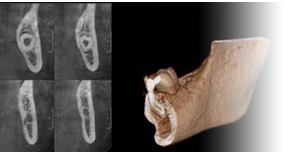

■レントゲン(CTを含む全顎の撮影)

患者さまの口腔内の状況を診断し、手術計画を立てます。歯科医師は患者さまに細かい情報を伝え、要望に添ってアドバイスを行い、抱いている疑問に対し明確にしてくれます。そして、レントゲンを撮り、手術計画を作成し、インプラントの埋入位置を決めます。